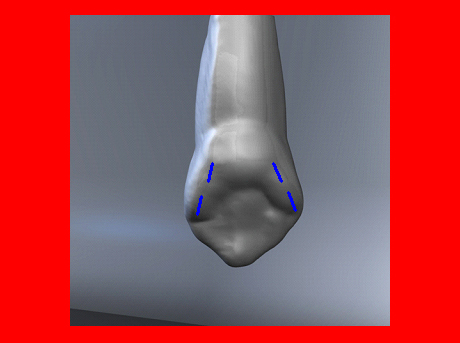

En ciertas áreas del saber humano, el lenguaje confuso o criptográfico Muchas son las técnicas elaboradas para lograr un desgaste selectivo, y numerosos autores han expuesto en su momento variadas formas de lograr una función oclusal fisiológica mediante el ajuste de la misma. Han pasado años desde entonces y, sin embargo, aún hoy, un altísimo porcentaje de profesionales “navega” por el mar de la confusión oclusal, dada la diversidad de conceptos y escuelas, sin lograr arribar a costa alguna donde poder anclar un conocimiento sólido sobre cómo tratar la oclusión Ya se esté realizando una simple obturación, endodoncia, incrustación, radectomía u ortodoncia, la lógica pocas veces, en la mayoría de los casos, vincula un tratamiento con otro, siendo el resultado final el mismo caos inicial; enmascarado por mucho tratamiento profesional. El ajuste oclusal es un medio inicial de proveer al sistema enfermo de: Dicha técnica, que puede ser terapéutica en sí misma; consta de dos etapas, a saber: 1) Ajuste Oclusal por Adición Mediante el estudio de la guía anterior, encargada de efectuar las Disclusiones durante las excursiones mandibulares, podremos observar si ésta es funcional o no. • Marcas de carácter continuo, si en ese recorrido se produce la Disclusión de los sectores posteriores y todo marcha correctamente. FIG 1-2 Si por el contrario observamos: • Marcas de carácter discontinuo, significa que dicha Disclusión se está efectuando por medio de una pieza dentaria posterior a la guía anterior. FIG 3-4-5 (FIGS. 3, 4 Y 5). En la figura 6 las flechas indican, en un caso clínico de análisis oclusal, la presencia de marcas discontinuas que indican Interferencias en Propulsiva. FIG 6-7 Y por último, si existieran: • Abrasiones de las áreas discluyentes en las áreas de diagnóstico de la guía anterior, deberemos aportar material a dicha zona para no permitir el choque lateral de las piezas posteriores (Ajuste Oclusal por Adición) En las imágenes 11 y 12 podemos observar la adición de composite en la punta de un canino derecho, previa la observación de la Faceta Parafuncional remarcada durante el análisis oclusal en el articulador. (FIGS. 8 A 12). 2) Ajuste oclusal por Sustracción o Desgaste Habiendo cumplido ya con la verificación de la funcionalidad de la Guía Anterior, comenzamos los desgastes en céntrica, a fin de lograr un único arco de cierre, guiado eficazmente por la Guía Anterior; es decir: la coincidencia entre Oclusión Habitual y Oclusión en Relación Céntrica. En este caso, intentar gastar dichos puntos, de ser posible sólo en las cúspides de corte o no fundamentales: • Crestas Triangulares Internas, Cúspides Vestíbulares Superiores • y un poco de las Crestas Triangulares Internas, Cúspides (FIGS. 13 A 16). Si la deflección es hacia el lado opuesto, se invierten los desgastes. En las migraciones hacia adelante, las únicas razones posibles están en los puntos estabilizadores (FIG. 17); es decir: -Vertientes Distales de los Rebordes Marginales, Triangulares (FIG 17) (FIG 18 A-B-C-D) Obsérvese cómo, en una boca prácticamente entera, comienzan a “desmoronarse” prismas adamantinos (FIG. 19), como consecuencia de un punto prematuro de contacto, ubicado en la posición de un estabilizador, que provoca la discrepancia horizontal postero-anterior causante de dicho efecto (FIG. 20). FIG 19-20 Dicho punto, será necesario ajustarlo antes de cualquier tratamiento en la zona ¿Cuáles serían las consecuencias si esos incisivos fueran implantados tal como es frecuente observar en múltiples congresos y cursos de implantología, donde el tema de la oclusión no es más que un cuadro polifacético y anecdótico? 14 15 16 17 Todo producto del adelantamiento mandibular Realizados ya los desgastes en céntrica, obteniendo de esta manera un único arco de cierre, es decir, oclusión en relación céntrica, debemos realizar el ajuste de las excéntricas, apoyando la acción de la guía anterior, para lo FIG 22 a. De un lado a otro de un mismo maxilar, la imagen es especular, o sea invertida. b. En hemimaxilares cruzados, la imagen es idéntica. Allí donde existan colisiones entre cúspides, se deberá crear un surco para que dicha cúspide antagonista migre a su través, tanto en el lado de no trabajo, como en el de trabajo y en el de propulsión. FIG 23 Es importante conservar esta parte del surco, ya que si no existieran, los contactos entre cúspides serían en superficie y no puntiformes (fig. 24). FIG 24 1. Obtener un único arco de cierre con coincidencia entre oclusión habitual y relación céntrica. 2. El cierre mandibular debe ser recibido sólo por la tabla premolar-molar. 3. Durante las excursiones funcionales es la guía anterior la que debe sufrir las fuerzas laterales. 4. De cumplirse estas dos premisas debemos obtener libertad de desplazamiento (no confundir con libertad en céntrica) a las piezas posteriores mediante la creación de surcos disclusivos. Examinadas ya las posibles migraciones mandibulares y los desgastes o aposiciones necesarios para poder ocluir en céntrica, es fundamental recordar que, previamente a todo tipo de ajuste, se ha hecho necesario ubicar a la mandíbula en relación céntrica. Para ello debemos utilizar el propio funcionalismo muscular 22 FIG 25 Y esto no significa otra cosa que: piezas dentarias estables en todos los planos del espacio, ATM centrada en la cavidad glenoidea, periodontos sin tensión, músculos en la dimensión de elongación adecuada para un fisiologismo Paz absoluta en la intimidad del Sistema Estomatognático. Y así, como corolario final, es posible establecer una regla de oro similar en importancia a la conocida formula: Forma = Función Ésta es: FIG 26 FUNDAMENTOS NEUROFISIOLÓGICOS DEL REGISTRO DE OCLUSIÓN EN RELACIÓN CÉNTRICA ( ORC) MEDIANTE EL USO DE LAMINILLAS DE LONG CUADRO

En el transcurso de dichas Lateralidades o Propulsiva, podremos ver:

En la figura 7, se muestran la Disclusión Inicial (durante el transcurso de la cual deben separarse por completo los sectores posteriores –flecha izquierda–, y la Disclusión Final de recorrido mucho más largo –flecha derecha–.